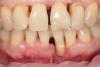

sergio Опубликовано 8 июня, 2013 Поделиться Опубликовано 8 июня, 2013 женщина,50 лет, 31 зуб сама вынимала из лунки и вставляла обратно несколько месяцев. Была сдержанна при разговоре,чтоб случайно не скаканул изо рта Не ходила к гигиенисту ,потому как уверена,что ее зубной камень держит зубы...(наверное она права) Теперь стоит вопрос с тактикой лечения в этой области. Гигиену слава богу уже сделали, зуб 3.1 фиксирован адгезивно к соседним. Фотографий внутриротовых пока нет. Я бы предложил ей убрать все 4 резца и имплантировать 4.2 и 3.2 ,в обл 3.1 - поработать с костью и мягкими тканями,чтоб создать условия для понтика... Пациентка хотела бы ограничиться костной пластикой в обл. 3.1 и постановкой одного импланта.ВАШИ ВАРИАНТЫ? 1.jpg2.jpg3.jpg4.jpg6.jpg8.jpg А 42 почему приговорили? Ссылка на комментарий

art.podzhigant Опубликовано 8 июня, 2013 Автор Поделиться Опубликовано 8 июня, 2013 (изменено) Бир,мягкими тканями имхо можно 3-4 мм нарастить,не больше! А имплантологическая ли вообще эта пациентка,с ее любовью к камням? И зачем вообще здесь все так усложнять? Эта зона эстетически не видна,зачем пациентке удалять еще соседние зубы и делать несколько операций?мне кажется,что лучше в данной ситуации адгезивный мост и все!удалить всегда успеется,а так она еще походит без ухудшения нынешней ситуации... приговорили 42 профилактически.после снятия фундамента в виде камней я ее еще не видел.возможно там теперь все шатается :-) У этой пациентки как раз все очень даже видно. при улыбке и разговоре. Во вторник фото сделаю выложу. Изменено 8 июня, 2013 пользователем art.podzhigant Ссылка на комментарий

art.podzhigant Опубликовано 11 июня, 2013 Автор Поделиться Опубликовано 11 июня, 2013 вот фотки.Пациентка выбрала план лечения с удалением зубов! Ссылка на комментарий